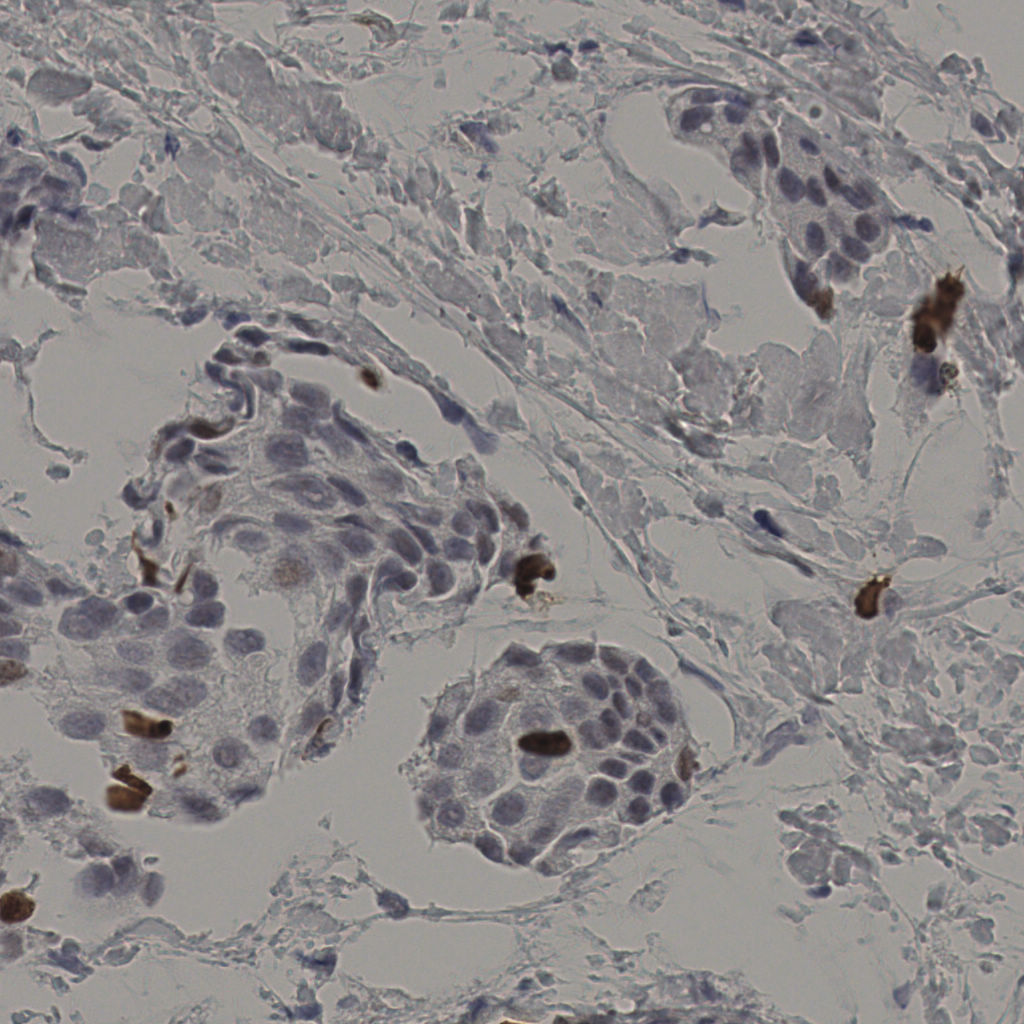

缩略图

标记后

标记前